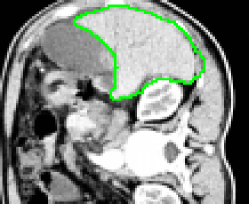

4.1 Metrication artifacts and minimal surfaces

We begin by comparing the CCMF segmentation result with the classical max-flow algorithm (graph cuts). Figure 3 shows the segmentation of a brain, in which the contours obtained by graph cuts are noticeably blocky in the areas of weak gradient, while the contours obtained by both AT-CMF and CCMF are smooth.